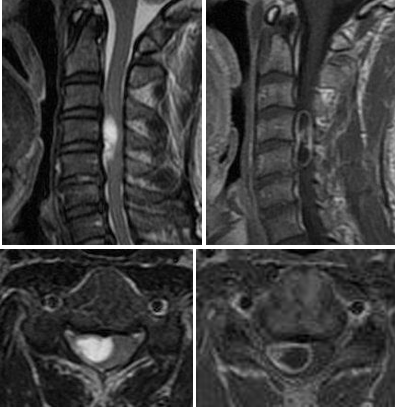

診断は、病歴と身体検査の後、MRIやCTなどの画像診断により行われます。これらの検査により腫瘍の位置、大きさ、脊髄への影響を評価します。

図 脊髄腫瘍(硬膜内髄外腫瘍)